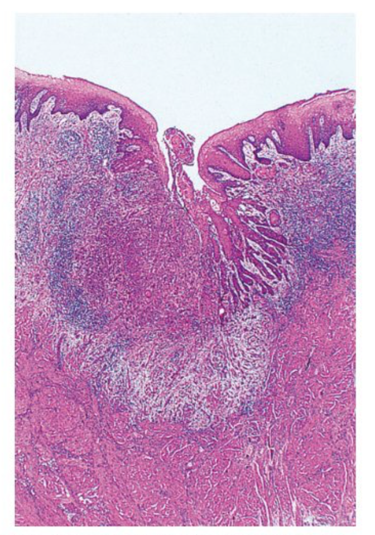

h&e - dermis of the skin. less packed collagen fibres, irregular arrangment to provide strength in many directions.

dense irregular